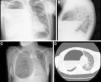

A 40-year-old man with no significant personal history consulted due to dyspnea and fever. Clinical laboratory tests showed leukocytosis with left shift and elevated acute phase reactants. Chest radiograph (Fig. 1A and B) and computed tomography (Fig. 1C and D) showed a cystic image with calcified walls and air-fluid level, occupying practically the entire right hemithorax, causing parenchymal atelectasis, and contralateral mediastinal shift. Treatment began with empirical antibiotics, and in view of the lack of response, the collection was drained by thoracotomy, with subsequent clinical improvement.

(A and B) Standard posteroanterior and lateral chest radiographs showing cystic lesion with calcified walls occupying practically all the right hemithorax containing an air-fluid level. (C and D) Chest computed tomography, showing that the cystic lesion was causing atelectasis of a large part of the pulmonary parenchyma of the right hemithorax and left mediastinal shift.